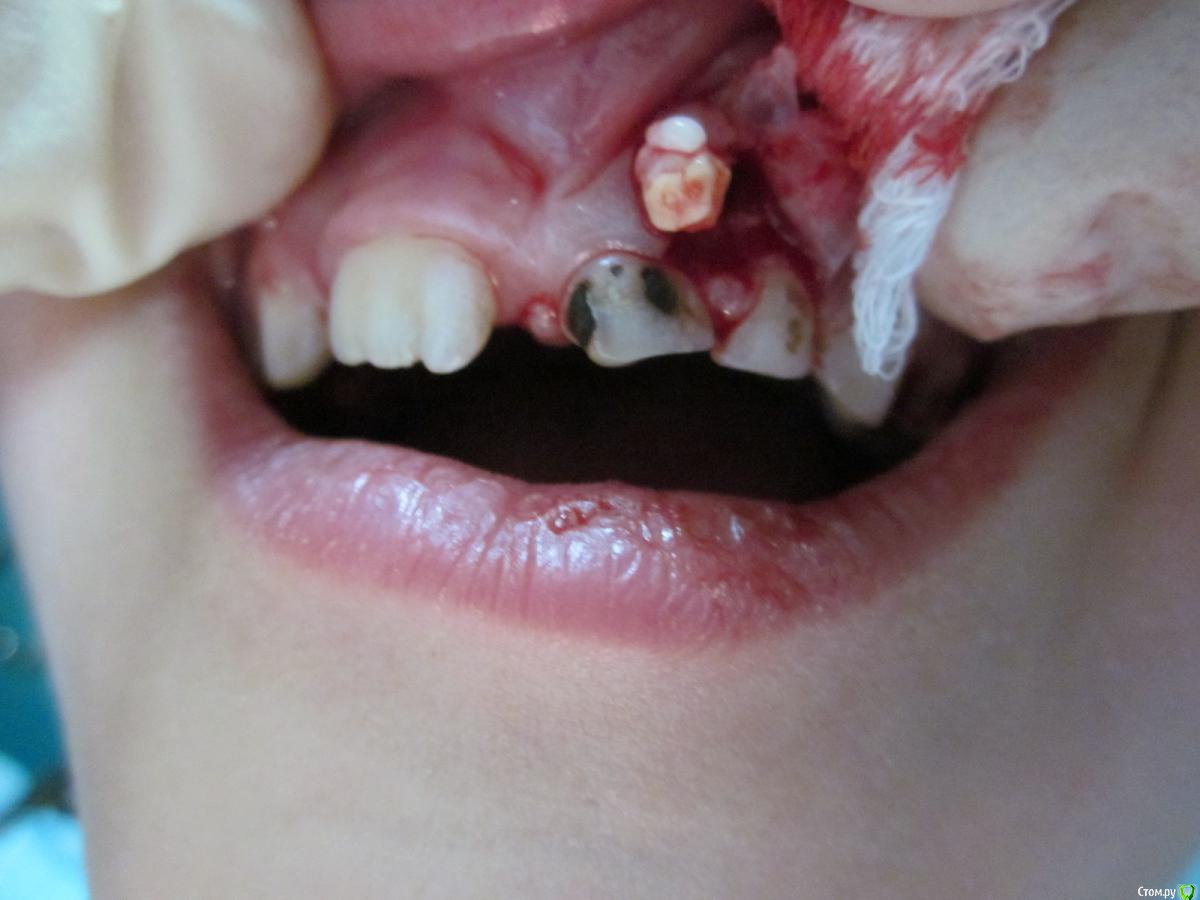

По данному случаю: пациент 6-7 лет, 21 не растёт, все динамят (ортодонты и терапевты), дошли до хирурга: на снимок прицельный, что то не то, на КТ охарактеризовал как одонтому. Операция под

анестезией Ультракаин дс, кортикальную пластинку трепанировал «расковырял» эскаватором, убрал конгломерат тведых тканей, саму оболочку, удалил 61. Биологический материал в пробирку с физ

раствором, направление на исследование в гистологию и ГОУ самим.